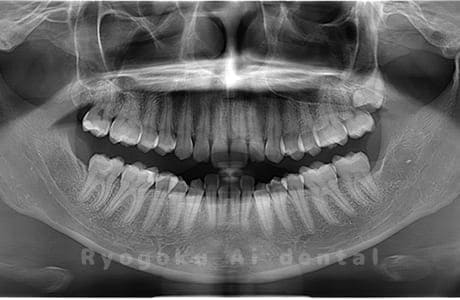

水平埋伏の親知らず

歯茎の中で完全に横に生えてしまうタイプです。

この親知らずを水平埋伏智歯と言います。このタイプはほとんどが下顎のケースです。真横に生えているので抜歯の際は難易度が高く2~3つに砕いて分けて抜歯をします。